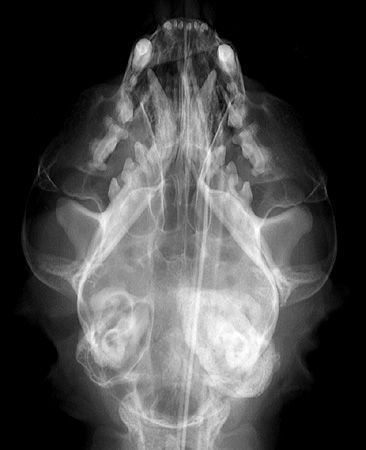

Radiograph of the Dorsoventral View

Figure 1: Dorsoventral view